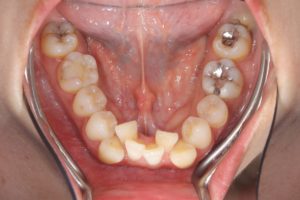

他にも

前突を伴わない重度叢生の症例でも

抜歯してスペースを確保することがあります。

治療前

第一小臼歯抜歯後1カ月経過。

中切歯と犬歯の間にオープンコイルを入れ

側切歯のスペース作り開始。